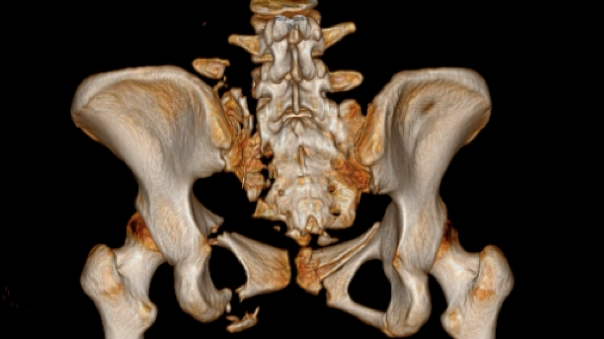

术前,手术团队进行了周密的准备,基于患者术前影像,借助基于AI与大数据的自动手术规划,将患者健侧肢体进行镜像配准,通过精细化自动分割与重建,实现个性化、定量化的复位规划。

图三:自动分割与重建

图四:人工智能复位规划